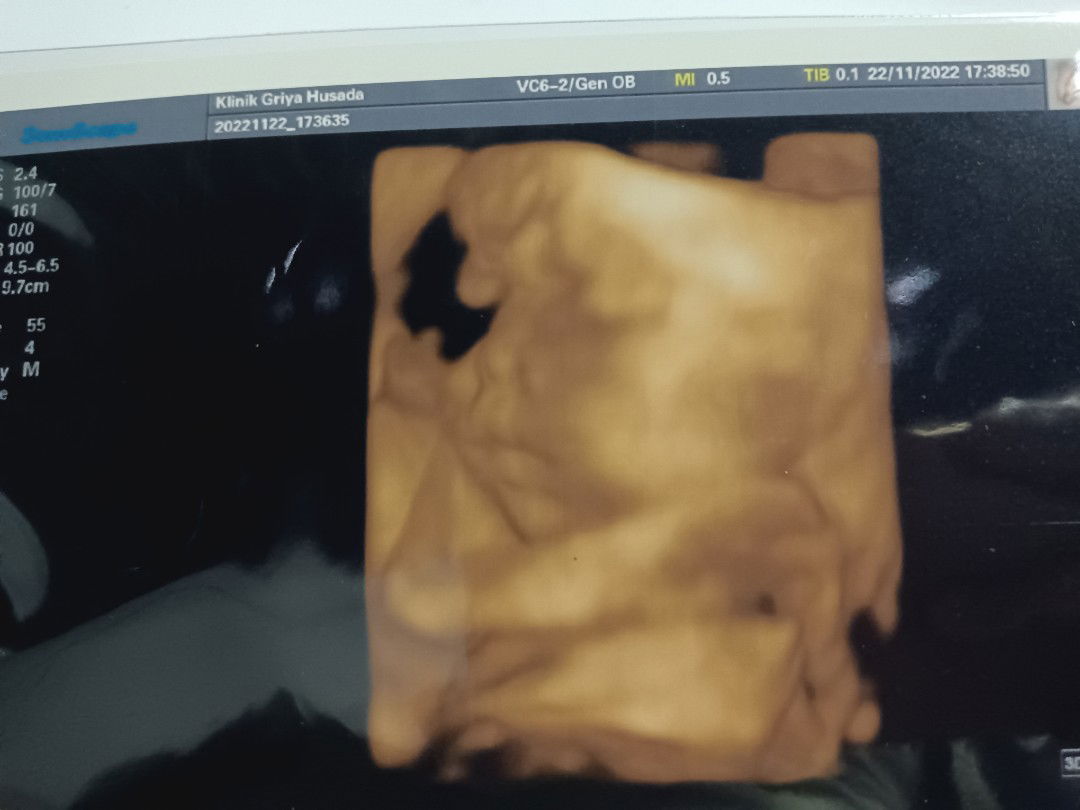

Baca lagimungkin sebenernya aktif tp posisi janinnya lg menghadap k arah yg kurang sensitif buat merasa gerakannya bun😅 soalnya suka begitu sii...kaya waktu itu saya uk26w jg pas bgt lg usg padahal saya g ngerasa janinnya bergerak tp d layar dia heboh bgt 😅🤭.. dokternya jg blg dia aktif bgt g mau diem padahal mau d liat mukanya tp d umpetin makin nunduk akhirnya g keliatan 🤣